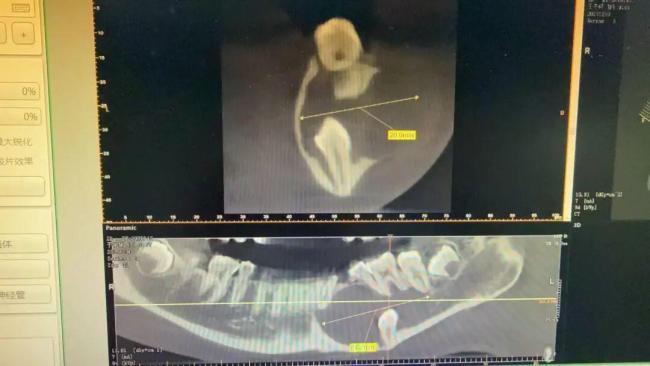

晶晶妈妈带着孩子焦急地找到宁波市第二医院口腔颌面外科副主任徐斌主任医师。经详细检查发现,晶晶下颌骨底部藏着一颗牙,下颌骨内的囊肿已达41.7mm×26mm,牢牢压迫着5颗恒牙的牙根,恒牙健康岌岌可危。

医生解释,这颗埋伏牙藏在牙槽骨里多年,长期隐匿未被发现,慢慢引发了囊肿,再不及时手术干预,不仅这5颗恒牙保不住,颌骨也会受到不可逆的损伤。如果采用传统治疗方法,晶晶需拔除5颗受影响的恒牙,这样不仅会严重影响口腔咀嚼功能,还会破坏面部美观。针对这颗巨大囊肿,常规的一次性刮除术也不适用于晶晶,存在三大风险:损伤正常恒牙牙根、误伤面部神经导致嘴唇麻木、造成大量骨缺损以及增加下颌骨意外骨折的可能。

结合晶晶的具体情况,徐斌团队为其制定了分期治疗方案:先通过减压引流法为囊肿“减压”,等待骨腔内新骨重新生长;待新骨长成后,再进行第二次手术彻底清除囊肿;最后通过正畸治疗,将紊乱的牙齿排齐,恢复口腔正常功能。听从了医生的建议,晶晶近日接受了微创手术,手术过程顺利且创伤极小。